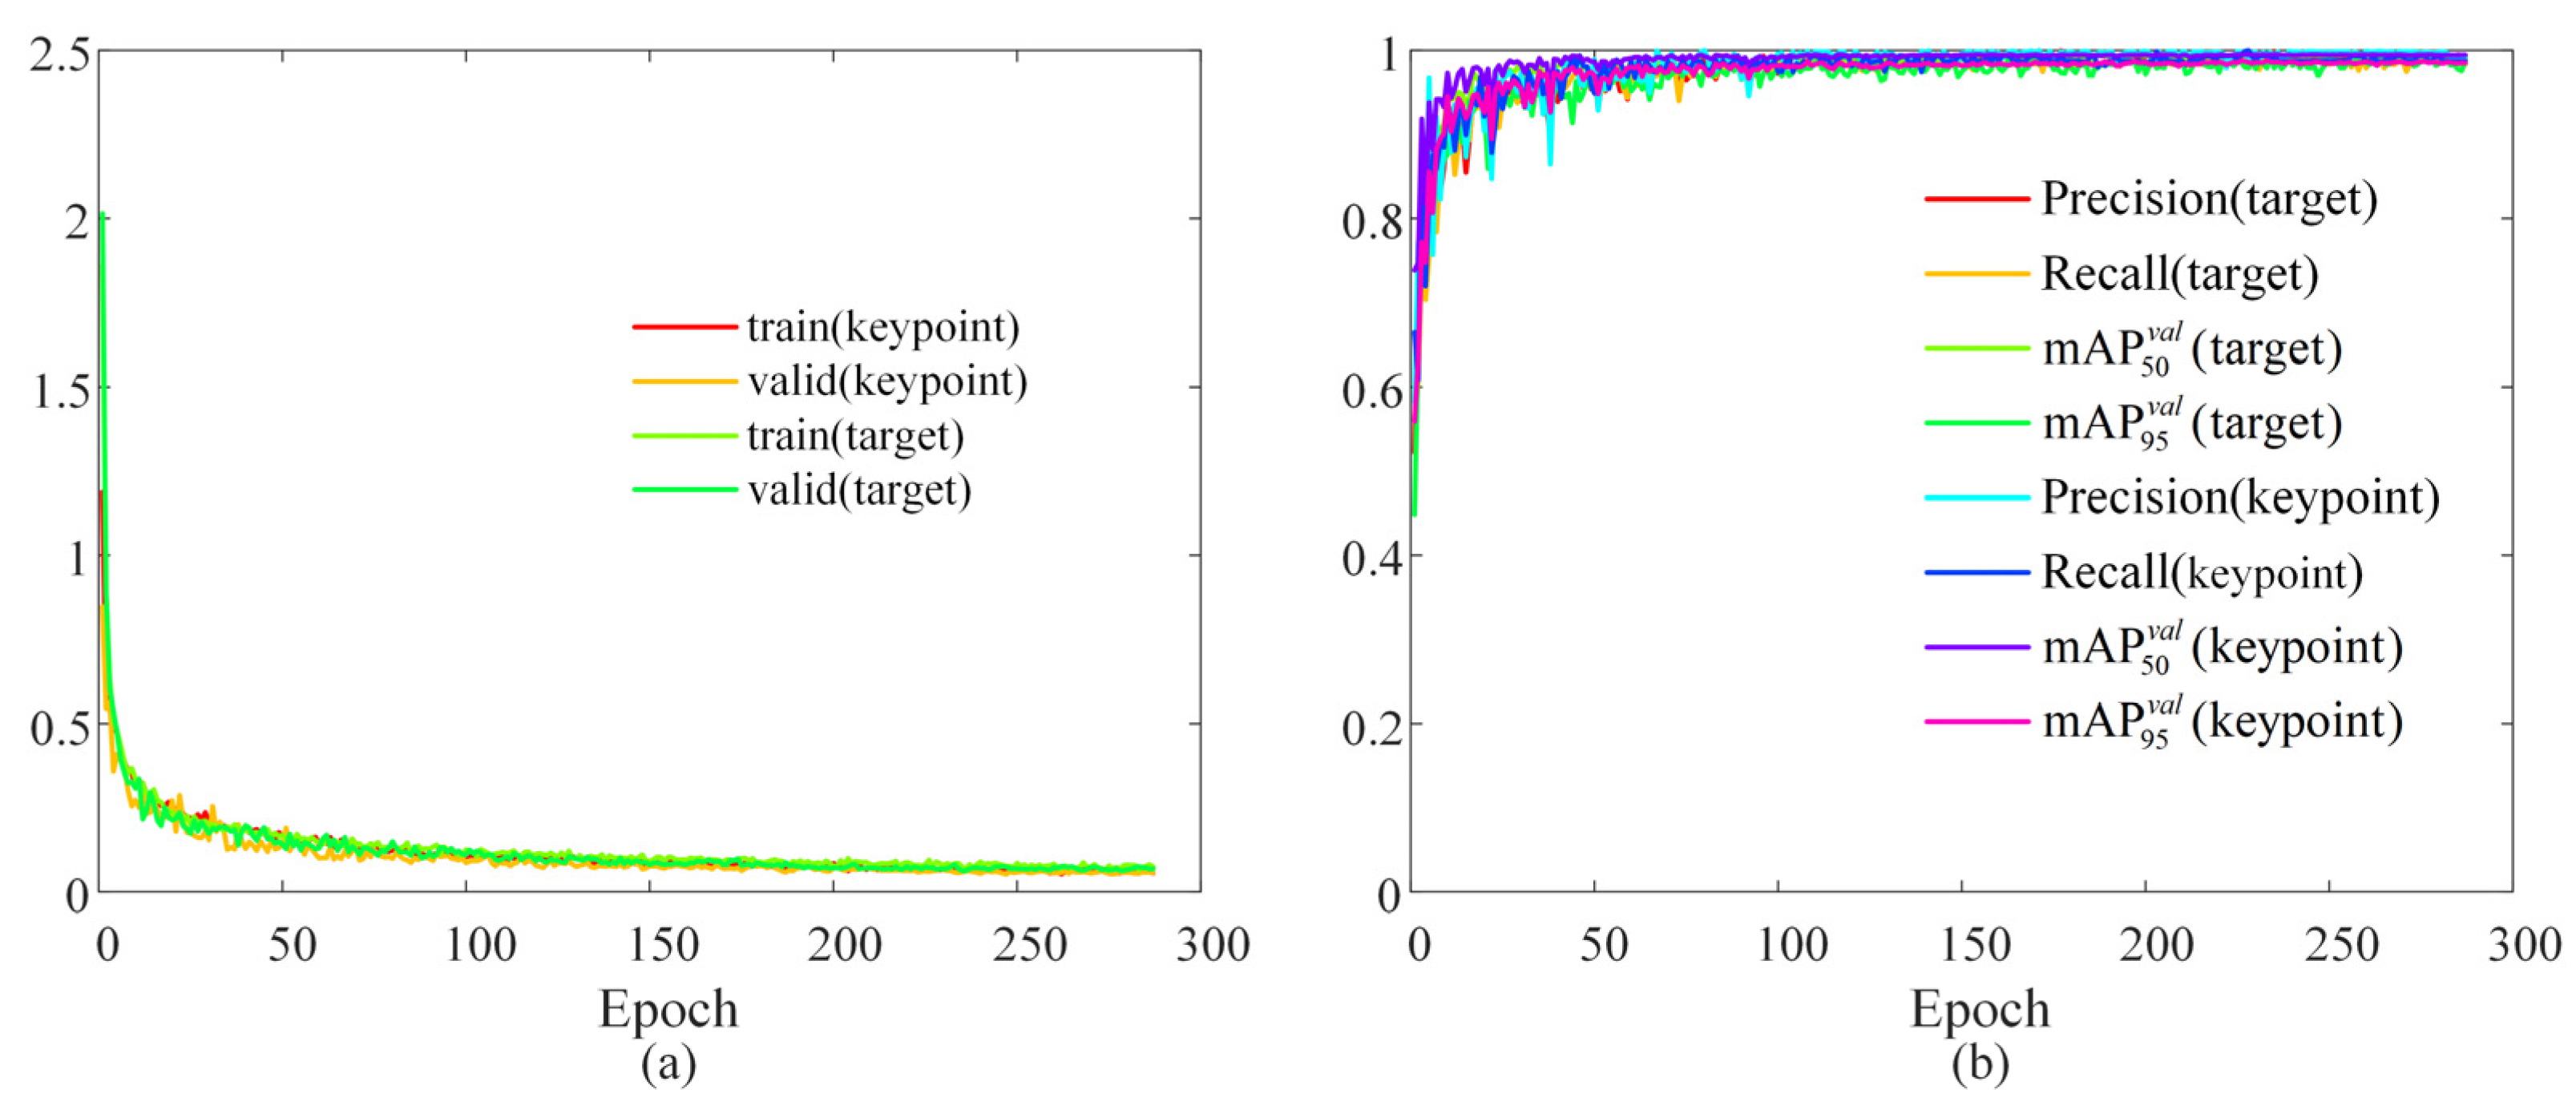

4.2. Surgical Scene Perception Network Training